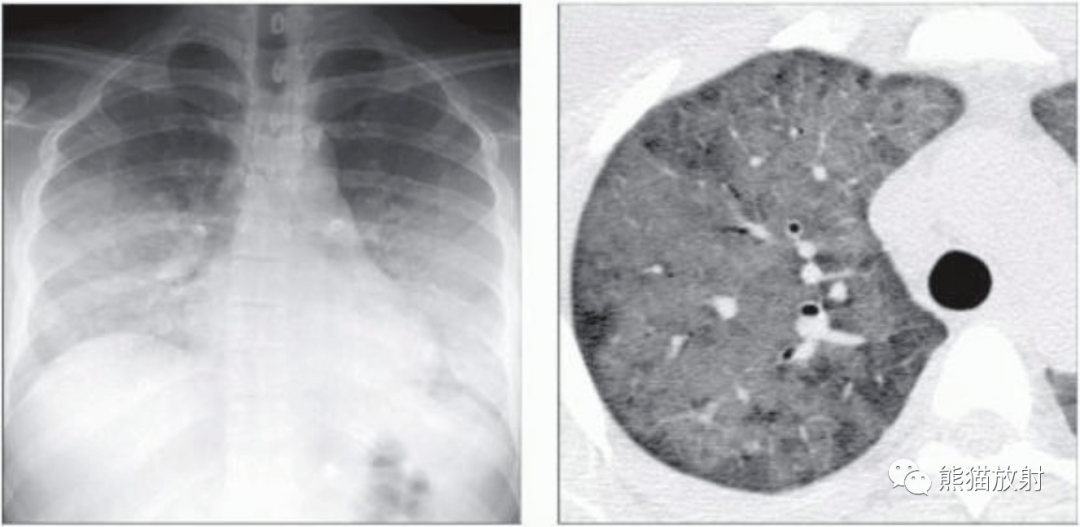

病案肺吸虫感染似肺癌复发

图片尺寸396x418

肺孢子菌肺炎卡肺肺寄生虫病丨影像表现

图片尺寸1080x527